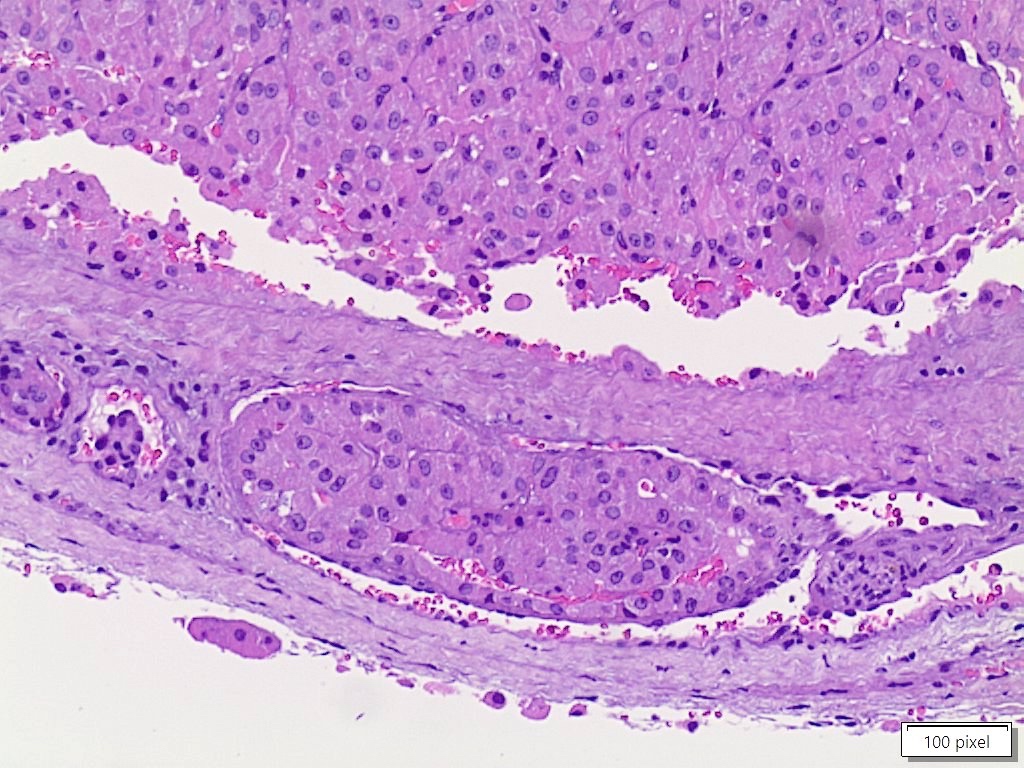

Www.pathologyoutlines.com